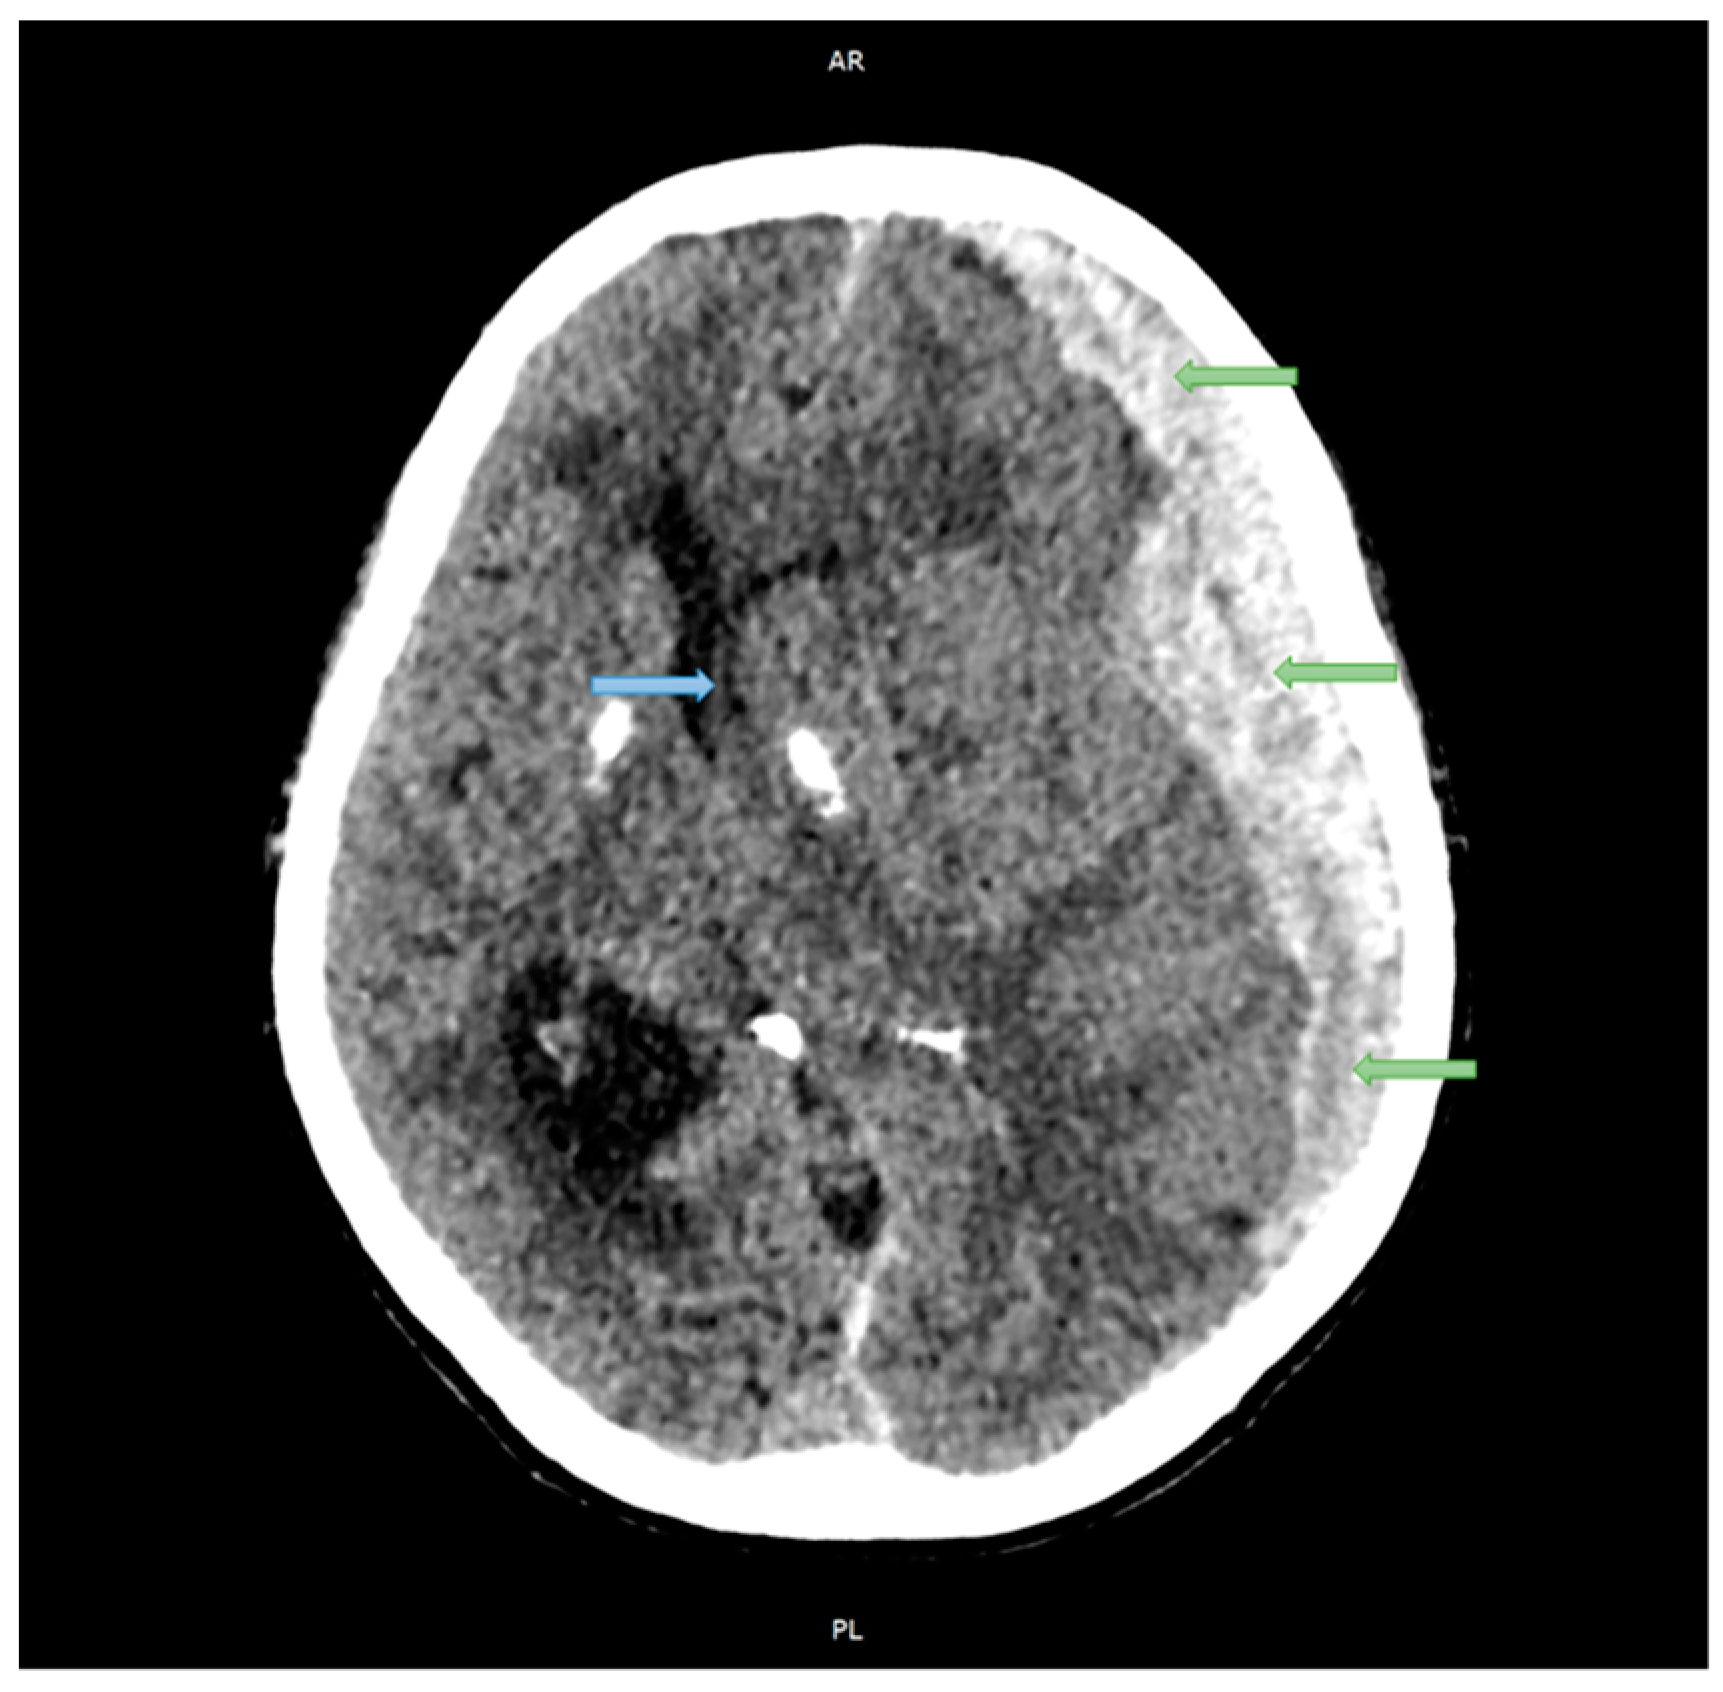

2.1. Case Studies